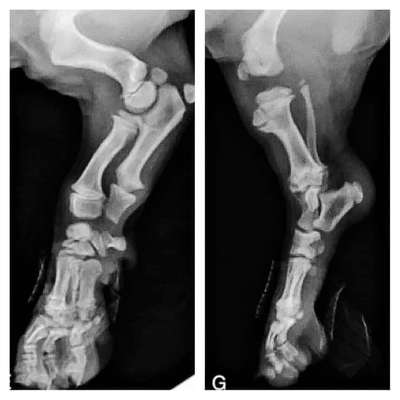

Wenn Sie Ihre 8 Wochen alten Welpen bekommen, behalten Sie bitte diese Bilder im Kopf. Ihre Knochen berühren sich noch nicht einmal. Sie stapfen so niedlich mit großen schlaffen Pfoten und wackeligen Bewegungen herum, weil ihre Gelenke nur aus Muskeln, Sehnen, Bändern und Haut bestehen. Noch passt nichts fest zusammen oder hat eine richtige Gelenkpfanne.

Wenn man sie in dieser Zeit übermäßig laufen lässt oder ihre Bewegung nicht einschränkt, um sie vor Überanstrengung zu schützen, gibt man ihnen keine Chance, richtig zu wachsen. Jeder große Sprung oder aufgeregtes Hüpfen und Laufen verursacht Stöße zwischen den Knochen. In einem vernünftigen Maß ist das nicht problematisch und gehört zur normalen Abnutzung, die jedes Tier erfährt.

Wenn Sie Ihren Welpen vom Sofa oder Bett auf und ab hüpfen lassen, mit ihm lange Spaziergänge/Wanderungen unternehmen, schädigen Sie das sich bildende Gelenk. Wenn Sie Ihren Welpen auf Fliesen ohne Bodenhaftung krabbeln lassen, schädigen Sie das Gelenk.

Man hat nur einmal die Chance, sie wachsen zu lassen. Ein gut gebauter Körper ist das Ergebnis einer hervorragenden Zucht und einer guten Erziehung - beides, nicht nur eines.

Sobald sie ausgewachsen sind, können Sie den Rest ihres Lebens mit Spielen und anstrengenderen Übungen verbringen. Lassen Sie es also ruhig angehen, solange sie noch kleine Baby-Welpen sind, und machen Sie ihnen das Geschenk, das man nur einmal machen kann.

Fotos Veteriankey.com @62 Tage

*Viele Knochen sind bis zum Alter von 13 Monaten noch nicht vollständig verwachsen.